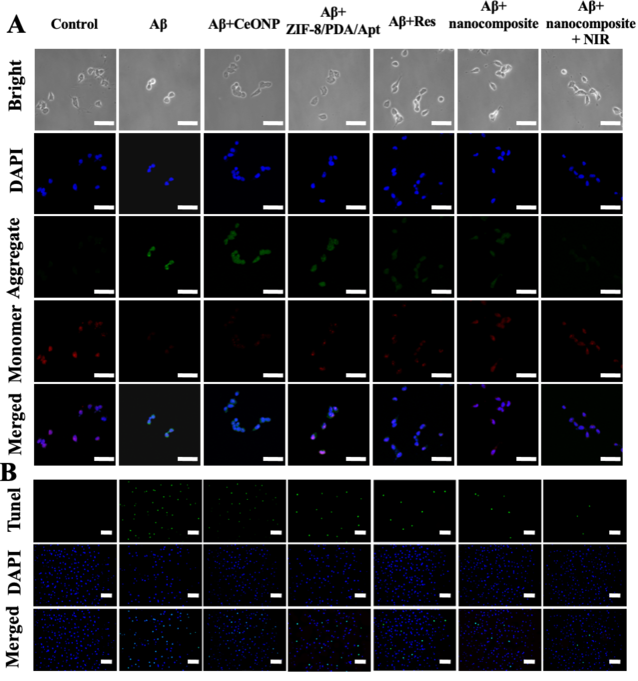

我們針對(duì)Aβ自聚集的現(xiàn)象,考察了該探針在抑制Aβ聚集以及解離原纖維方面的療效。ThT和TEM結(jié)果表明(圖四),探針既能夠抑制Aβ單體聚集,又能解聚Aβ原纖維,并且在光熱照射下,該性能能夠得到增強(qiáng)。細(xì)胞內(nèi)治療結(jié)果表明,該探針能夠在細(xì)胞水平,有效抑制Aβ單體聚集,清除AβO誘導(dǎo)的細(xì)胞內(nèi)過(guò)量ROS,并且探針的光熱性能,能夠增強(qiáng)其治療效果(圖五)。此外,JC-1、TUNEL以及Calcium-AM/PI染色結(jié)果均表明,該探針可以有效地保護(hù)神經(jīng)細(xì)胞免于Aβ誘導(dǎo)產(chǎn)生的凋亡。

【圖五】探針在細(xì)胞水平的治療效果考察